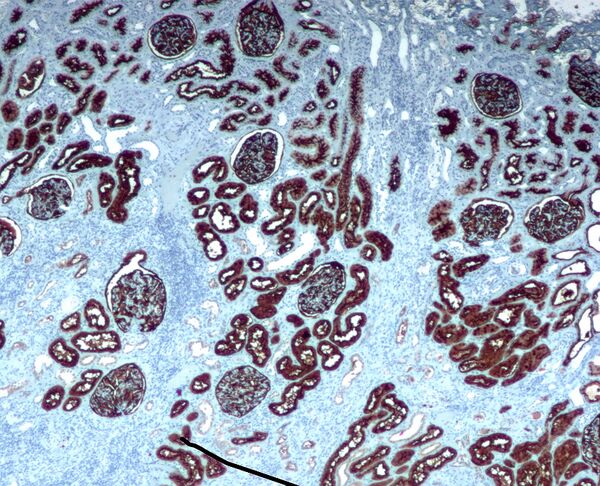

Неприлизин экспрессируется широким спектром тканей, но особенно высокий уровень белка обнаружен в почках. Это частый антиген, обнаруживаемый при остром лимфобластном лейкозе, и является важным маркёром при диагностике заболеваний у человека. Представлен на лейкемических клетках пре-B-лимфоцитарного фенотипа, которые представлены в 85 % всех случаев острого лимфобластного лейкоза[5].

CD10 применяется при гематологической диагностике, поскольку белок экспрессирован на ранних B-, про-B- и пре-B-лимфоцитах и в герминативном центре лимфатических узлов[7]. Гематологические заболевания с положительным тестом на CD10/ALL включают ангиоиммунобластную T-клеточную лимфому, лимфому Беркитта, хронический миелоидный лейкоз в бластном кризе (90 %), диффузную B-крупноклеточную лимфому, клетки фолликул лимфоузла (70 %). Острый миелоидный лейкоз, хронический лимфолейкоз, мантийноклеточная лимфома и B-клеточная лимфома маргинальной зоны характеризуются отрицательным тестом на CD10. CD10 отсутствует на клетках лимфомы, происходящих из зрелых B-клеток[8].